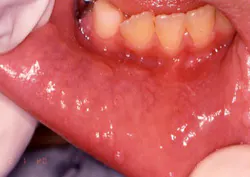

Your patient today is a 10-year-old boy, Jason, who presents to your office with his mother. The mother is concerned about the small papules that are visible on the mucosa along the vestibular areas of lips. The papules appear to be slightly raised, sessile, and almost the same color as the surrounding tissue. Jason reports no pain, but has traumatized the growths several times in the past few months. The mother reports that the growths appear to “come and go” (see Figure 1).

Perioral and intraoral characteristics: The lesions of focal epithelial hyperplasia display a pink to whitish, somewhat translucent surface that is only slightly cauliflower-like. They are soft on palpation, as they generally have less keratin than the other HPV-related lesions. The lesions most commonly affect the lips, tongue, and buccal mucosa, where they appear as numerous discrete papular or nodular growths that may be singular or in multiple lesions.

Distinguishing characteristics: These lesions may be more generalized within the oral cavity than the other forms of HPV.